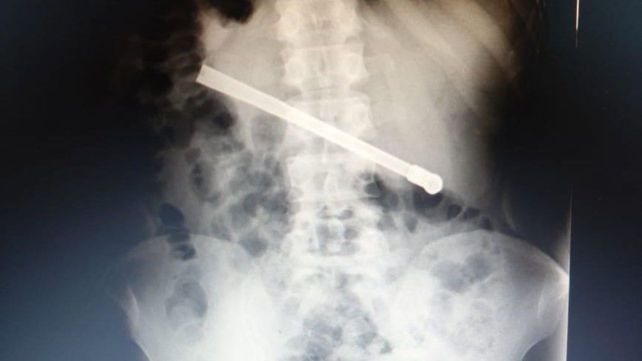

La radiografía mostró que tenía una bombilla

Un preso que se encuentra alojado en el Complejo Penitenciario Rosario (CPR) se tragó una bombilla de mate y tuvo que ser operado en el hospital Eva Perón. El hombre, de 35 años, tenía el objeto atravesado en el tórax y fue intervenido quirúrgicamente este martes.

Al continuar con el malestar, le realizaron una placa radiográfica en la Unidad Penitenciaria ubicada en 27 de Febrero al 7800, y pudieron determinar que había ingerido una bombilla de mate que quedó alojada transversalmente en la cavidad torácica.